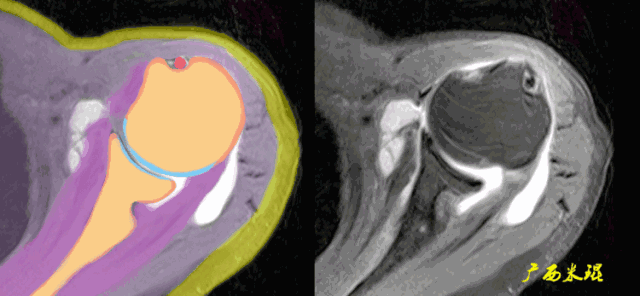

肩袖(Rotator cuff)损伤由Smith于1834年发现并命名,指组成肩袖的冈上肌、冈下肌、肩胛下肌和小圆肌的损伤。肩袖是以上4条肌腱共同组成的功能复合体,呈一个袖套状包绕肱骨头,维持盂肱关节的稳定,同时提供肩关节活动时所需的动力。

冈上肌和冈下肌在肱骨大结节上有共同止点,冈上肌和肩胛下肌在结节间沟处共同包绕肱二头肌长头腱。这样紧密的关系预示着肩袖的某一部分组织发生病变一般都会波及其余的肩袖组织,也是我们MRI阅片中必须要注意的。

正常肩袖的MRI表现

各个序列肩袖均表现为均匀的低信号,是肌腱的延续。